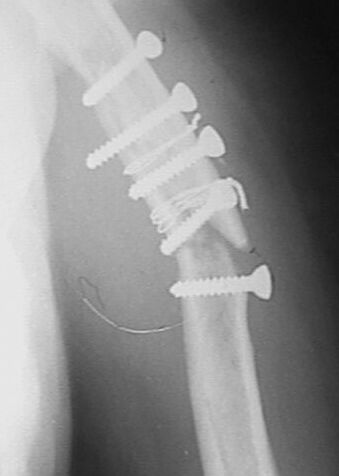

фас+профилькосые

Больная оперирована в апреле 2002 г, иммобилизация в течение 3 месяцев.После операции были явления неврита лучевого нерва, которые в последующем исчезли. Во время проведения ЛФК отмечает появление болей. В настоящий момент имеется патологическая подвижность в месте перелома, деформация плеча. У нас мнения разделились в тактике дальнейшего ведения.

1. провести репозицию закрытую и продолжить иммобилизацию гипсовой повязкой.мотивируя опасностью повторного повреждения лучевого нерва при повторной операции.2. провести открытую репозицию, удаление фиксаторов, остеосинтез накостный костной пластикой.3. репозиция, фиксация отломков аппаратом внешней фиксации спицестержневого типа.